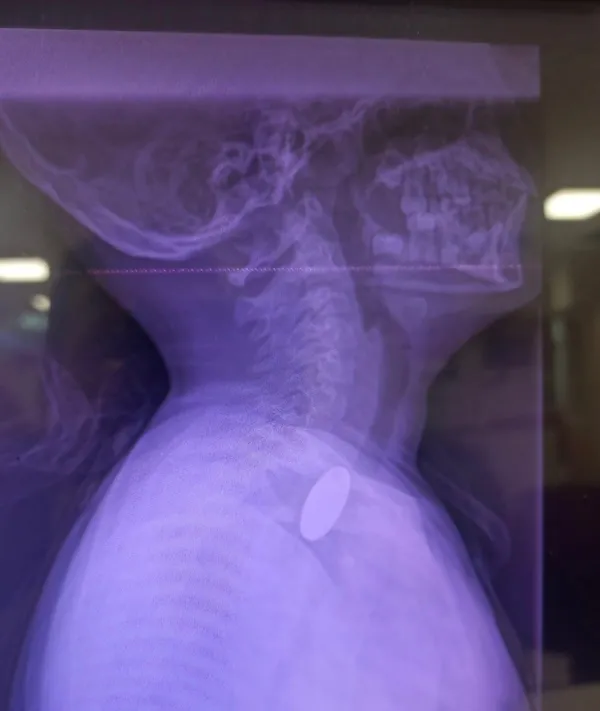

Edinilen bilgilere göre, yabancı cisim yutma şikâyetiyle hastaneye başvuran küçük hasta, yapılan ilk değerlendirme ve görüntüleme tetkiklerinin ardından ilgili branşlar tarafından operasyona alındı. Y.K.'nin yemek borusuna kadar ilerlediği tespit edilen madeni paranın çıkarılması için Gastroenteroloji Uzmanı Dr. Yaren Dirik ile Kulak Burun Boğaz (KBB) Hekimi Dr. Yasin Gökçınar tarafından ortak bir girişim gerçekleştirildi.

Siirt Eğitim ve Araştırma Hastanesi Başhekim Yardımcısı Uzman Dr. Burak Özkan, konuya ilişkin yaptığı açıklamada çocuk hastalarda yabancı cisim yutma vakalarının ciddi riskler oluşturabileceğine dikkat çekerek, "Hastanemize başvuran 8 yaşındaki hastamızın yemek borusuna kaçan madeni para, gastroenteroloji ve KBB ekiplerimizin koordineli ve titiz çalışmasıyla herhangi bir komplikasyona yol açmadan başarılı bir şekilde çıkarılmıştır. Operasyon süreci sorunsuz geçmiş olup hastamızın genel durumu iyidir," ifadelerini kullandı. Operasyonun ardından bir süre gözlem altında tutulan Y.K.'nin tedavisinin tamamlandığı, genel sağlık durumunun iyi olduğu ve herhangi bir ek probleme rastlanmadığı bildirildi. Küçük hasta, gerekli kontrollerin ardından sağlıklı bir şekilde taburcu edildi.